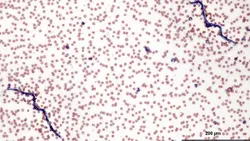

Collection of a peripheral blood sample allows a practitioner the opportunity to perform a complete blood count (CBC), which includes automated analysis of the blood and microscopic evaluation of the peripheral blood smear.

The peripheral blood smear (blood film) not only confirms and refines numeric data reported by the hematology analyzer, but also adds useful information when evaluated by a trained microscopist:

Each of the following cases highlight different reasons why it remains important for trained personnel to examine blood films even when an advanced, automated hematology analyzer is used to obtain data.

A 3.5-year-old, castrated male French bulldog was diagnosed with acute onset congestive heart failure. Table 1 provides blood analysis results; Figures 4 and 5 show the blood films.

Figure 4: Low-power scanning reveals 2 microfilariae. Leukocytes are moderately increased with numerous band neutrophils present along with a lesser number of segmented neutrophils, 2 monocytes, and 1 eosinophil. Erythrocyte density is moderately decreased consistent with numeric RBC data; 1+ anisocytosis and 1+ polychromasia are also present. Platelets are mildly decreased, which is consistent with thrombocytopenia. (_Wright-Giemsa, 20×)_

Featured Image

Figure 5: Closer magnification of Figure 4 reveals 2+ toxicity in many band neutrophils; 1 band is 3+ toxic (far right). Erythrocyte density is moderately reduced with 1+ anisocytosis, 1+ polychromasia, and a single nucleated RBC (upper left). Platelets are mildly decreased and there are 2 RBC fragments, including a schistocyte (left). (_Wright-Giemsa, 50×)_